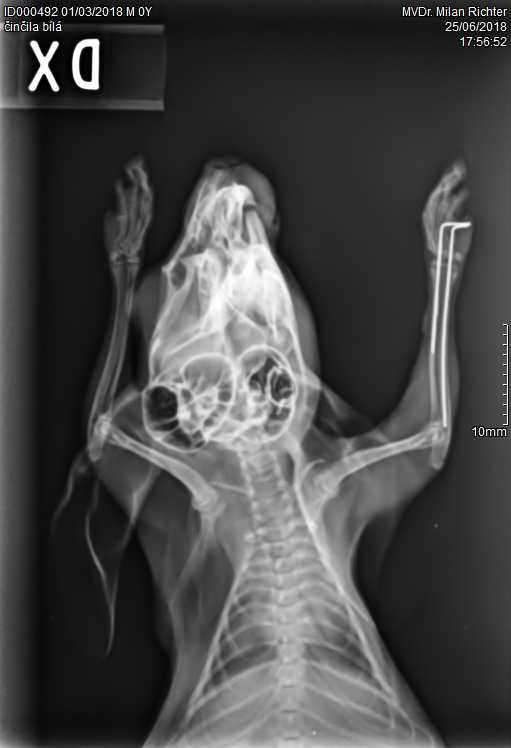

Velmi komplikovaná fraktura obou předloketních kostí u drobné činčily, jelikož se tak drobné implatáty běžně nevyrábějí, řešili jsme ji implantací nitrodřeňových hřebů vyrobených z injekčních jehel. Pacient se kompletně a bez následků uzdravil, po vyjmutí hřebů nožičku naplno používá.